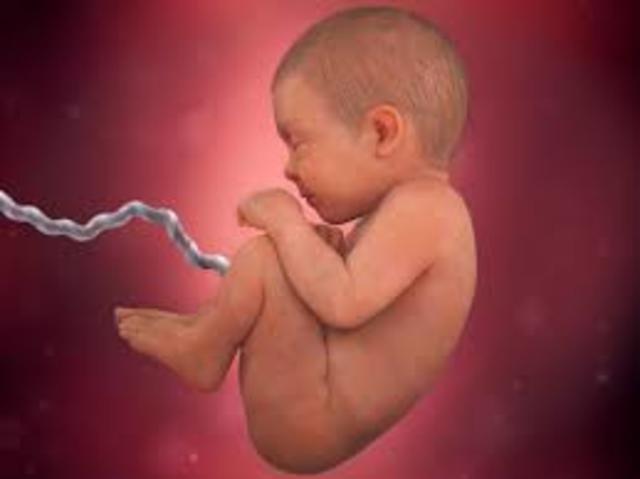

• the end of the fetus period

the end of the fetus period

Third trimester ends- at week 38 its eyes might change color. Its about 6.8 pounds, has firm grasp. At week 40 the baby is ready to come out weighing about 7 1/2 pounds. Full term pregnancy. Skull bones are not yet fused and this allows it to fit into the birth canal.